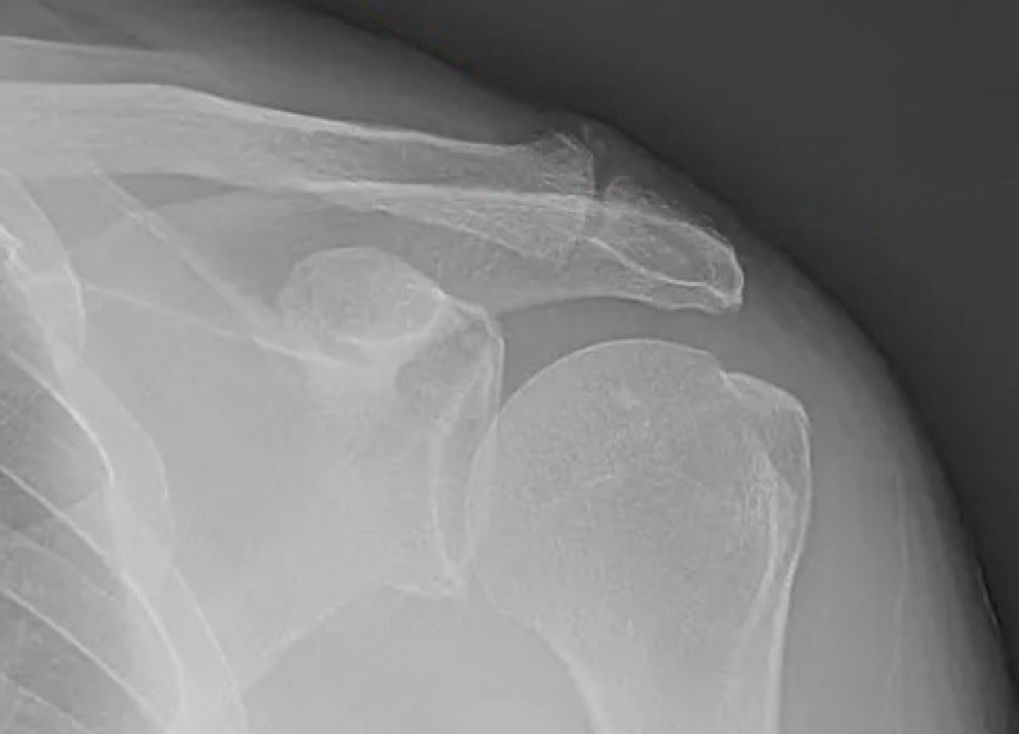

Shoulder radiographs demonstrating "AC" arthritis